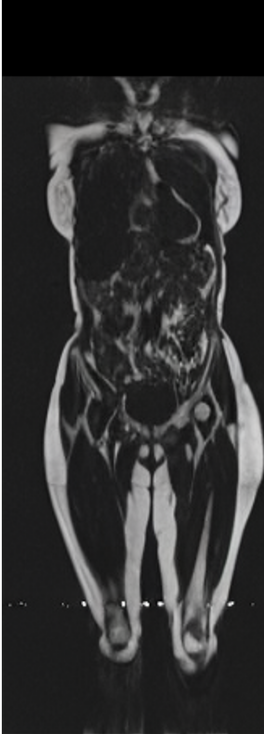

Our results unequivocally highlight the superior performance of X-Diffusion in terms of both qualitative and quantitative metrics. Representative MRI volumes generated by our pipeline, when juxtaposed with ground-truth images, showcased remarkable similarity, with even intricate physiological features like tumor information, spine curvature, and fat distribution being accurately captured.

Notably, X-Diffusion achieves state-of-the-art dB for a few input slices while baselines require more than 60 input slices to achieve similar performance (Figure 7). The margin is more than 12 dB PSNR for the 1-slice input in both the BRATS and the UK Biobank benchmarks (see Table 1 and Figure 6). For reference, two randomly sampled MRIs from UK Biobank would have a PSNR of 15.95 dB 0.36 (on 4800 randomly sampled examples). Omitting the preprocessing step of alignment DXA to MRI, leads to a drop of PSNR on average by 2.87 dB (29.01 dB 26.14 dB). The slices from 3D reconstructed volumes at varying depths and axis of rotation, visually match the ground truths for both brain and whole-body scans (see Figures 4 and 5 left). We also plot the error map (Figure 3) and the spread of the error (Figure 5 right) of such X-Diffusion generations to highlight the differences with the ground truth MRIs.

Preservation of Spine Curvature. For the spine segmentation on UK Biobank, we use a UNet++ model [83] with Dice Loss. We use a model trained to predict curves on DXA on UK Biobank [11]). We measure the Pearson correlation factor [11] of spine curvature measured on the generated MRIs where the input is a single MRI coronal slice, a single sagittal slice, or from the paired DXA, against the curvature of reference real MRIs of the same samples. The correlation coefficients are 0.89 for the coronal MRIs, 0.88 for the sagittal MRIs, and 0.87 for the DXAs on the test set of 308 human-annotated angles. We can then bin the curvature of the spines under different scoliosis categories based on human-annotated angles: mild: , moderate: , and severe . We show the results in Figure 8. This illustrates that the generated MRIs preserve the spine curvature from normal to severe scoliosis cases. Additional details about spine curvature are provided in supplementary material.

B.4 Preservation of Spine Curvature and Fat

For the spine segmentation on UK Biobank, we use a UNet++ model [83] with Dice Loss. We use a model trained to predict curves on DXA on UK Biobank [11]. We show in Figure IX that generated MRIs preserve the spine curvature from normal to severe scoliosis cases. We also study the case when DXA is used to generate the MRIs and show in Figure IX how the correlation to real curvatures compares to the input MRI case. The curvatures of the MRI generated from the coronal plane match the DXA curvatures more than the curvatures generated from sagittal MRI. This is expected since the antero-posterior plane of DXA is equivalent to the coronal plane for MRIs. This also explains the greater Pearson’s correlation coefficient of the coronal MRI (0.89) and DXA-generated curvature (0.88) compared to sagittal-generated curvature (0.87) relative to the reference curvature on the coronal plane. We observe though that MRI generation using X-Diffusion from another plane than the conventional plane for scoliosis assessment is valid.